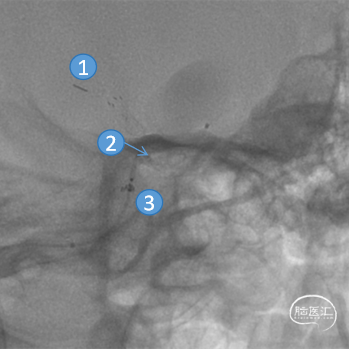

FRED®血流导向密网支架释放至覆盖动脉瘤颈后,通过微导管头端标记点与支架近端标记点预估支架释放的近端着陆点(约为两点之间的40%-60%)。确定近端着陆点处于血管平直区后,平衡释放支架末端,保证支架近端贴壁良好。

①支架远端标记点

②微导管头端标记点

③支架近端标记点

完全释放FRED 4017血流导向密网支架辅助弹簧圈栓塞后,正、侧位及3D造影观察,载瘤动脉通畅、支架贴壁良好、动脉瘤内造影剂滞留。